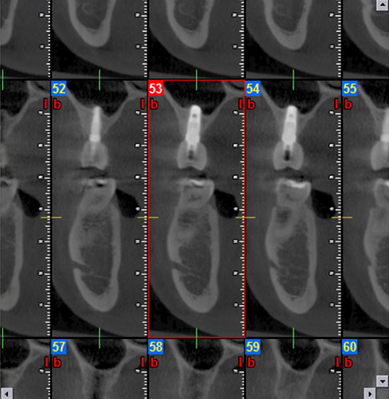

Hochmoderne 3D-Diagnostik in Kassel zur millimetergenauen Planung von Zahnimplantaten.

Detaillierte Darstellung verschiedener Knochenquerschnitte für eine sichere Chirurgie in Kassel.